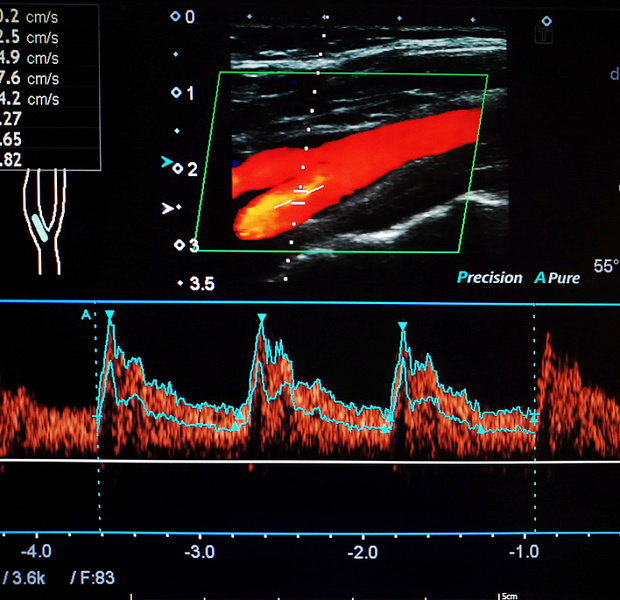

Самым информативным способом выявления ОАИ является доплеровское исследования с целью обнаружения атеросклеротических поражений сосудов.

На основании клинических проявлений и доплеровского исследования выделяют 4 функциональных класса ишемии органов пищеварения, которые совпадают со стадиями течения ОАИ.